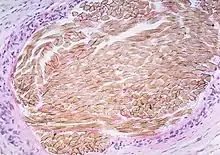

Picture of a granuloma (without necrosis) as seen through a microscope on a glass slide: The tissue on the slide is stained with two standard dyes (hematoxylin: blue, eosin: pink) to make it visible. The granuloma in this picture was found in a lymph node of a patient with a Mycobacterium avium infection. | |

Macrophages (specifically histiocytes) are the cells that define a granuloma. They often fuse to form multinucleated giant cells (Langhans giant cell).[7] The macrophages in granulomas are often referred to as "epithelioid". This term refers to the vague resemblance of these macrophages to epithelial cells. Epithelioid macrophages differ from ordinary macrophages in that they have elongated nuclei that often resemble the sole of a slipper or shoe. They also have larger nuclei than ordinary macrophages, and their cytoplasm is typically pinker when stained with eosin. These changes are thought to be a consequence of "activation" of the macrophage by the offending antigen.

The other key term in the above definition is the word "organized" which refers to a tight, ball-like formation. The macrophages in these formations are typically so tightly clustered that the borders of individual cells are difficult to appreciate. Loosely dispersed macrophages are not considered to be granulomas.